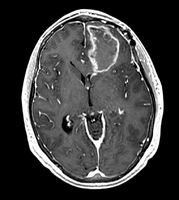

• inner part of the tumor segmented from SPGR

• outer part of the tumor segmented from post-Gad

• WM and GM segmented from N4-processed SPGR (WM segmentation of the original SPGR volume is included, note under-segmented WM in the skull base)

• all segmentations were done using FastMarching, fiducials are included for each of the segmentations

• no fine-tuning of the fiducial locations was done -- this is an example result one can get almost right away

• rule of thumb in placing fiducials: try to cover uniformly the volume you are trying to segment; this is particularly important for large structures like WM/GM